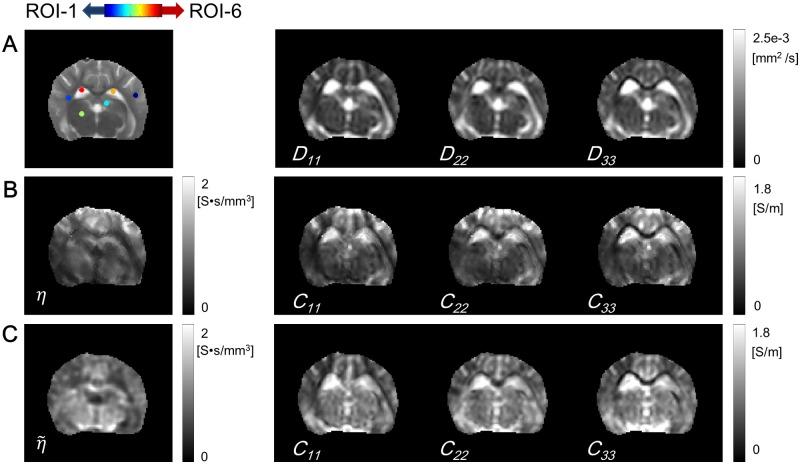

Transcranial direct current stimulation (tDCS) is a widely used non-invasive brain stimulation technique by applying low-frequency weak direct current via electrodes attached on the head. The tDCS using a fixed current between 1 and 2 mA has relied on computational modelings to achieve optimal stimulation effects. Recently, by measuring the tDCS current induced magnetic field using an MRI scanner, the internal current pathway has been successfully recovered. However, up to now, there is no technique to visualize electrical properties including the electrical anisotropic conductivity, effective extracellular ion-concentration, and electric field using only the tDCS current in-vivo. By measuring the apparent diffusion coefficient (ADC) and the magnetic flux density induced by the tDCS, we propose a method to visualize the electrical properties. We reconstruct the scale parameter, which connects the anisotropic conductivity tensor to the diffusion tensor of water molecules, by introducing a repetitive scheme called the diffusion tensor J-substitution algorithm using the recovered current density and the measured ADCs. We investigate the proposed method to explain why the iterative scheme converges to the internal conductivity. We verified the proposed method with an anesthetized canine brain to visualize electrical properties including the electrical properties by tDCS current.

经颅直流电刺激(tDCS)是一种广泛应用的非侵入性脑刺激技术,通过在头部贴附电极施加低频弱直流电来实现。使用 1 到 2 mA 固定电流的 tDCS 依赖于计算模型来实现最佳的刺激效果。最近,通过使用 MRI 扫描仪测量 tDCS 电流感应磁场,已经成功恢复了内部电流通路。然而,到目前为止,还没有技术可以仅使用体内 tDCS 电流可视化包括各向异性电导率、有效细胞外离子浓度和电场在内的电特性。通过测量 tDCS 诱导的表观扩散系数(ADC)和磁通密度,我们提出了一种可视化电特性的方法。我们通过引入一种称为扩散张量 J 替代算法的重复方案,利用恢复的电流密度和测量的 ADC 值来重建连接各向异性电导率张量和水分子扩散张量的比例参数。我们研究了该方法,以解释为什么迭代方案可以收敛到内部电导率。我们使用麻醉犬脑验证了该方法,以可视化包括 tDCS 电流在内的电特性。